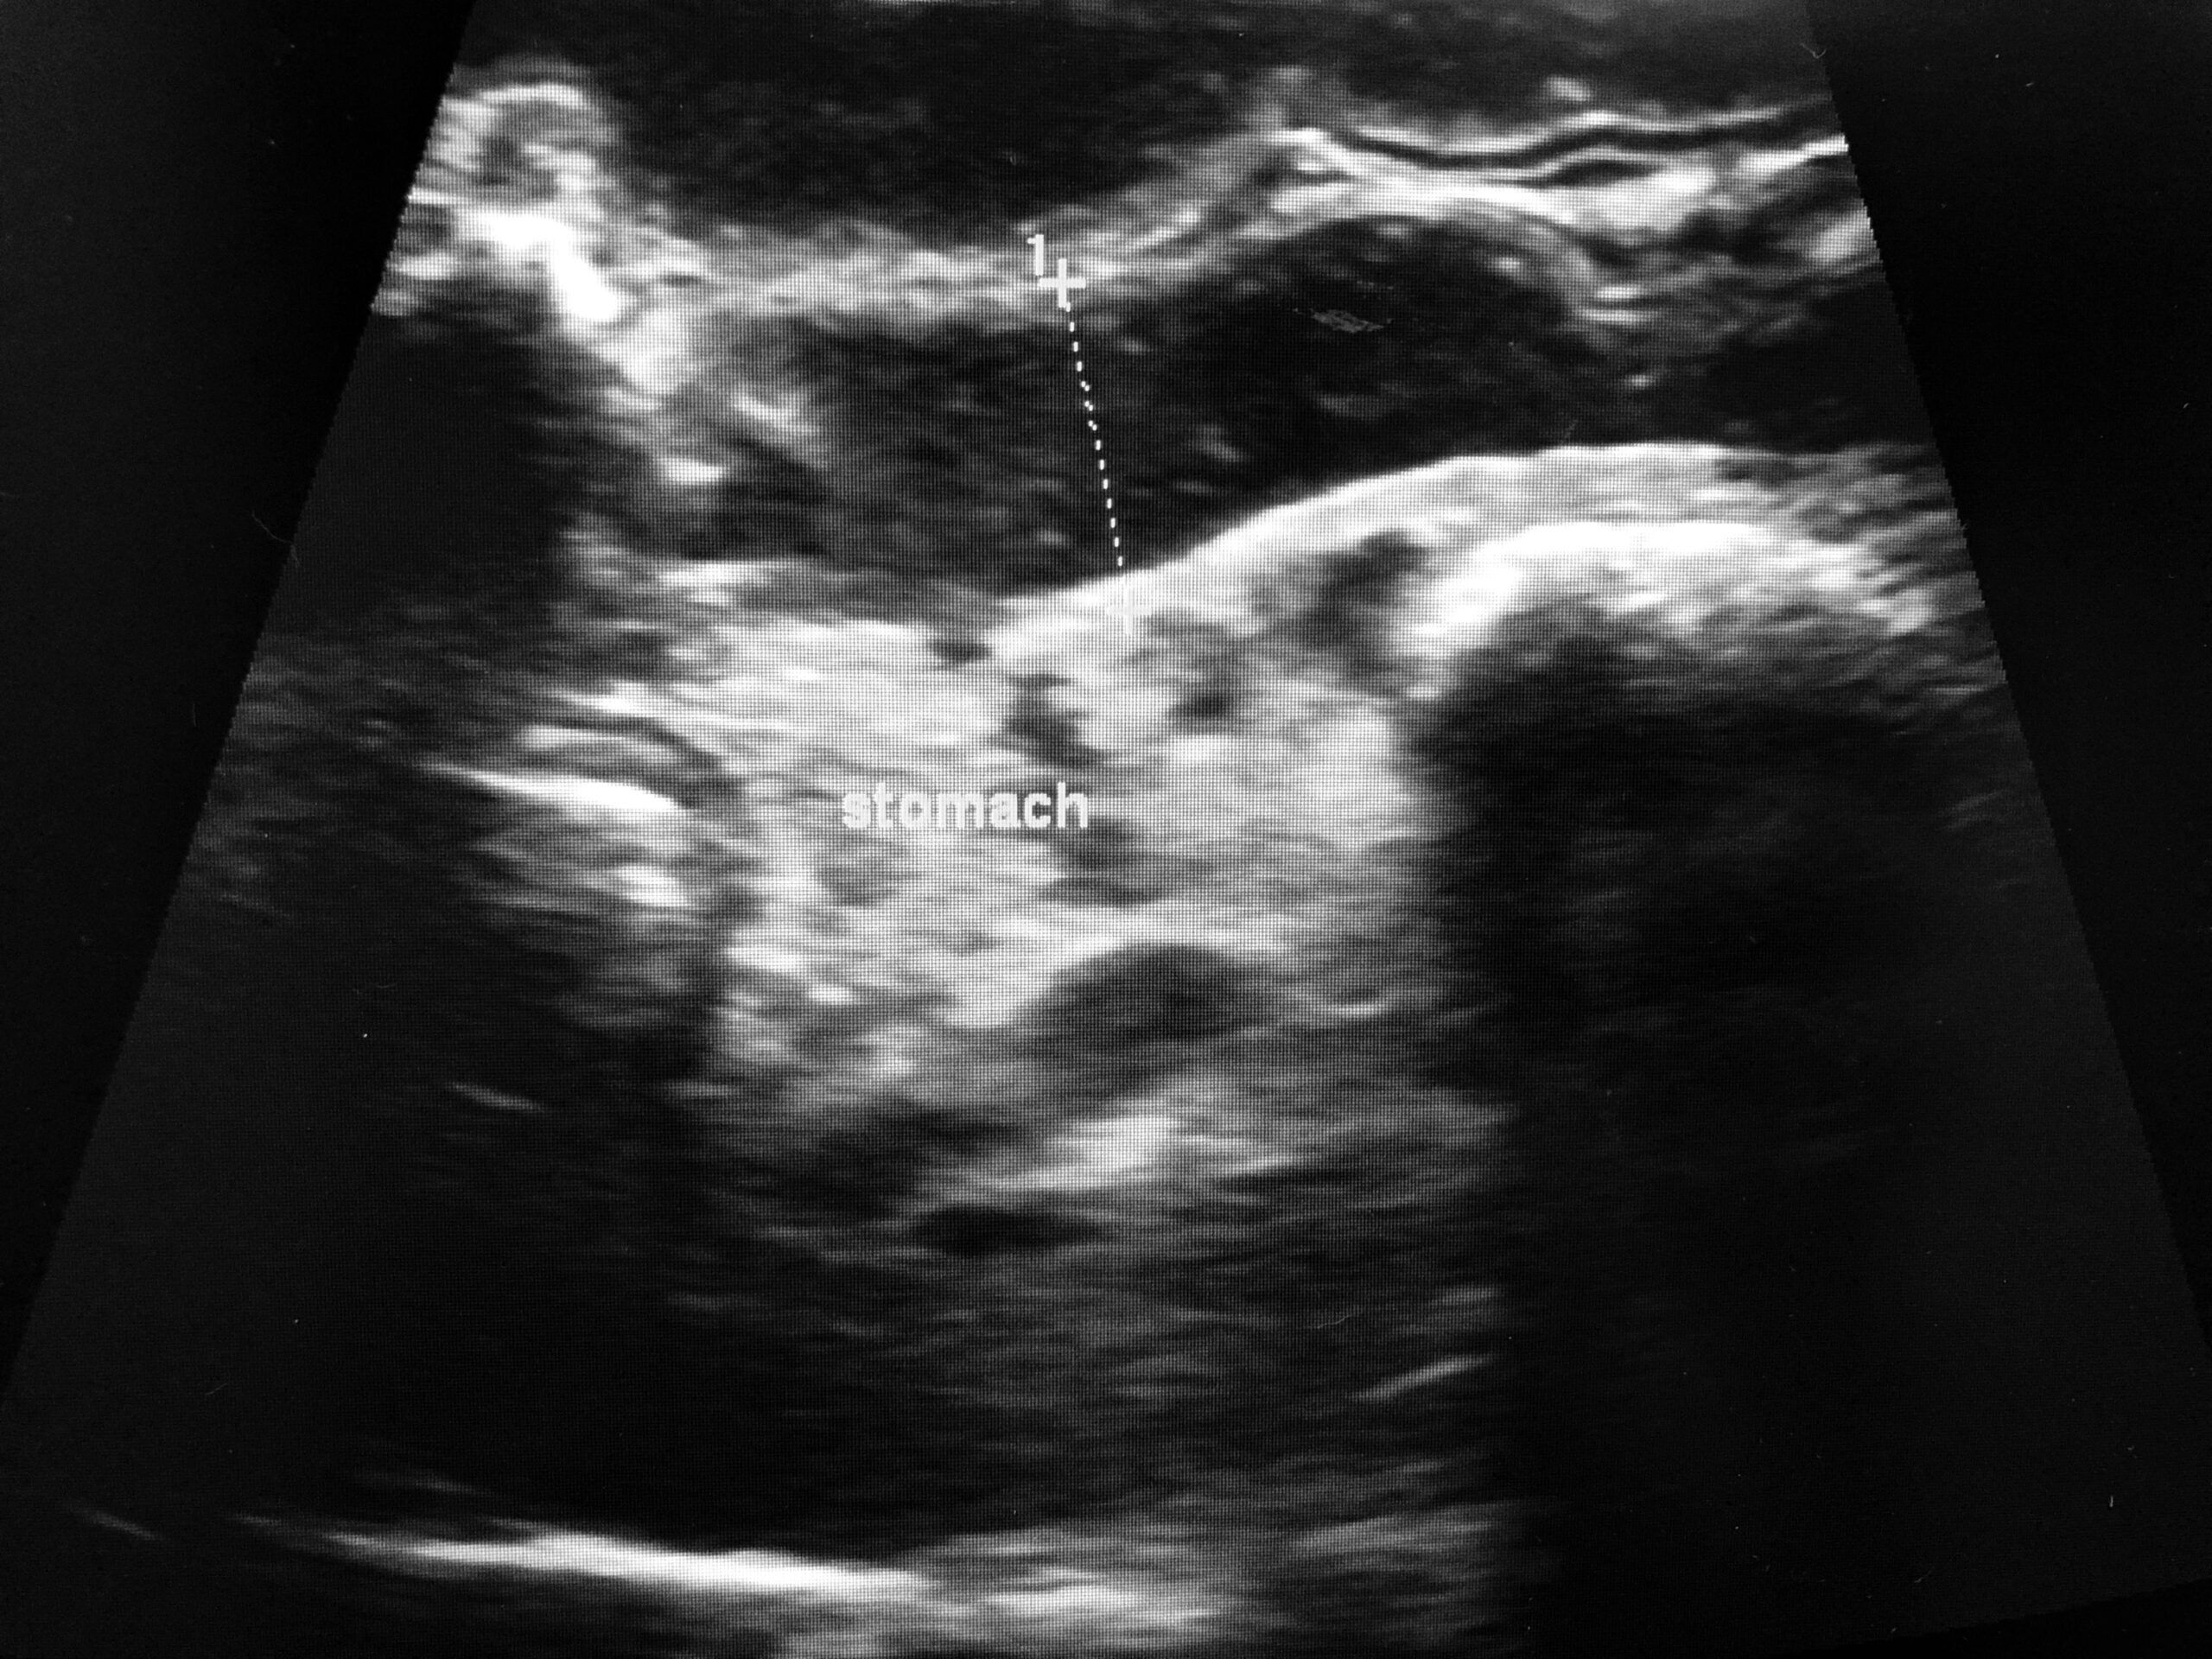

Yes, dogs can get stomach ulcers. Stomach ulcers develop when the stomach’s digestive juices start eating away the interior lining of the stomach wall.

Digestive juice is acidic and helps break down food. The stomach is lined with a protective mucosal barrier in healthy dogs.

Ulcers form when the mucosal barrier is faulty, leaving the inside of the stomach wall exposed to acidic digestive juices.

Stomach ulcers are defects in the inner lining of the stomach wall. Stomach ulcers in dogs are painful and potentially life-threatening.

Common stomach ulcer symptoms include melena (dark and tarry stool with blood), vomiting, reduced appetite, dehydration, weight loss, lethargy, and weakness.